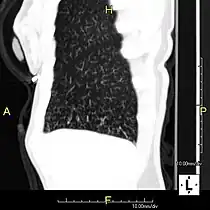

Oblique sagittal CT image showing lower lobe cylindrical bronchiectasis -